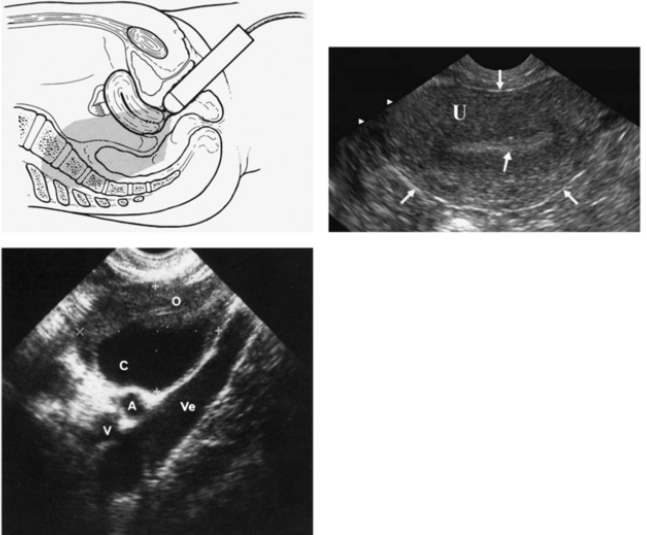

Существуют два основных подхода. Трансабдоминальный датчик скользит по передней брюшной стенке и даёт обзорную картину; для чёткости пациентке предлагают наполнить мочевой пузырь. Трансвагинальный датчик вводят во влагалище на небольшую глубину: пустой пузырь и близость зонда к органам обеспечивают более детальную визуализацию матки, эндометрия и яичников. Оба варианта могут дополняться допплеровским режимом, позволяющим оценивать кровоток.

Что именно видно на экране

На УЗИ врач определяет размеры, форму и контуры матки, толщину и структуру эндометрия, положение и эхогенность яичников, наличие доминантного фолликула или жёлтого тела, а также возможные кисты, миомы, полипы, очаги эндометриоза и свободную жидкость в полости таза. При необходимости измеряется скорость кровотока, что помогает отличить доброкачественные процессы от злокачественных. Специалистам и практикующим врачам рекомендуем онлайн тесты по УЗИ.